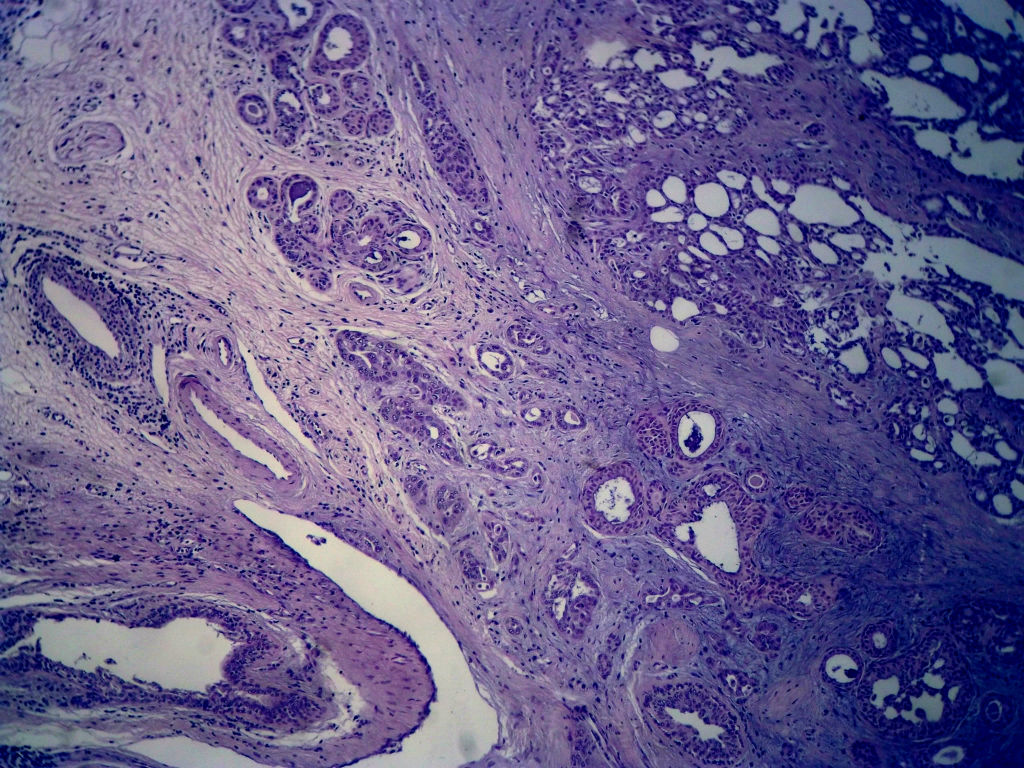

今天的一例术中冰冻。女,49岁,乳腺肿块。人气不旺,换个标题

腺病?癌?其他?(12楼常规,24楼免疫组化及会诊结果)图1

标签:浸润性导管癌 分泌癌 硬化性腺病

多谢强版主,这可是俺亲自全程操作的一张片子,俺的一点小经验是“组织要干”,“冷冻要快”,这个病例有点考验俺的神经,发上来听听高手们的意见。大体是乳腺组织一块,切面见一质硬结节,直径2cm,边界欠清,切面灰白色。强版别光夸片子漂亮啊,留下你的高见才放行

1. Most likely no invasive cancer

2 Sclerosing adenosis

3 Ductal epithelial hyperplasia

4. Bundles d Smooth muscle?

导管是乎可见双层上皮,部分上皮增生并有一定异型,考虑硬化性腺病,待石蜡。

导管可见双层上皮,部分上皮增生并有一定异型,考虑硬化性腺病

腺体与腺体之间的对比差异太大,不放心,不除外是癌,如果是我的病例,再次取材冰冻

后取的恶性特征明显多了,神经内分泌癌?

浸润性导管癌

浸润性导管癌。冰冻切片的诊断是很困难,直接诊断癌风险很大,但是在明显正常的导管间这种成片、成巢有腔的细胞团块也不是良性的表现,有的还似乎有围绕正常导管生长的倾向。诊断ADH还可以,但是不能归到任何一种DCIS的生长方式里。这例值得我好好学习。